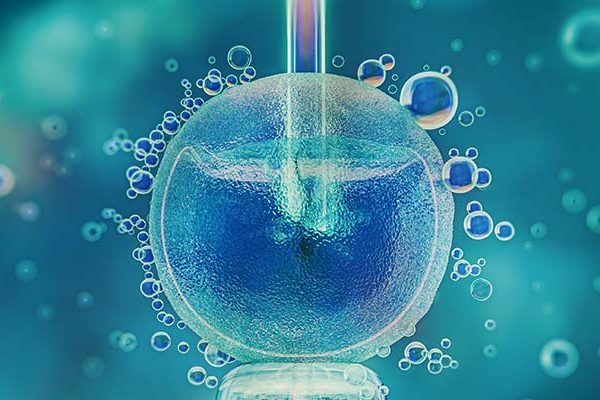

Infertility is a condition affecting millions of people worldwide, often in silence and solitude. For many couples, the path to parenthood is not always straightforward, and understanding how common infertility…